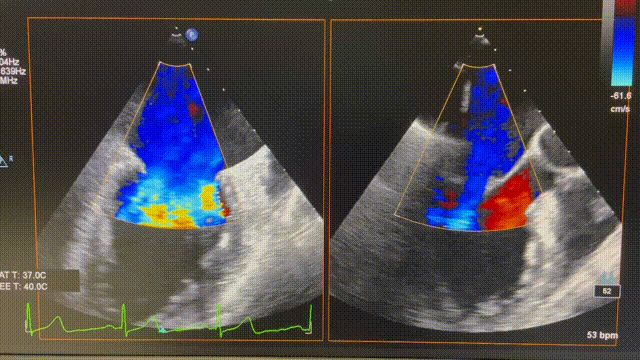

患者为74岁女性。术前心超显示后叶P2脱垂,伴极重度二尖瓣反流(VCW 9mm*16mm),图2。患者全麻后,在超声和射线引导下器械经股静脉穿刺房间隔,通过输送系统送入患者左心房,到达二尖瓣膜反流处,在经食道超声及DSA引导下,术者通过反复评估二尖瓣膜脱垂范围、抓捕位置、反流程度,精准夹合,成功植入1枚ValveClasp瓣膜夹。术后即刻左房压力及V波减低,患者反流从5+减少到1+(图3),跨二尖瓣平均压差3mmHg,肺静脉逆流消失,血流动力学改善明显,手术取得圆满成功。

图2 术前心超图。